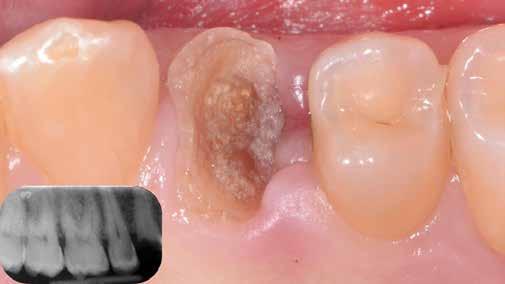

A mindennapi gyakorlatban gyakran találkozunk súlyos fogszuvasodással. A fogorvosnak mindig kihívást jelent a döntés, hogy kihúzzuk és implantátummal pótoljuk, vagy megmentjük a fogat, de kétséges a hosszú távú prognózis. Számos cikkből tudjuk, mint például Seltzer és Kim (Comparison of Long term survival of implant and endodontically treated teeth J Dent Res 93(1):19-26, 2014) cikke, hogy a fogak viszszanyerése jobb megoldás, különösen a fiatalabb betegeknél. A kirakós hiányzó kulcsa az általános fogorvos számára gyakran a maradó fogazat jó biomechanikai értékelése. Az endodontikusan kezelt fogak kudarcainak többsége valójában mechanikai hibákhoz, például repedéshez és töréshez kapcsolódik. A maradó fogszerkezet gondos biomechanikai értékelése, valamint a mechanikai teljesítményt javító technikákra való összpontosítás a legfontosabb a hosszú távú eredmény keresésében. A szerző praxisában a vertikális pre-

Egy 35 éves kaukázusi férfi páciens az 1.4-es fog (felső első premoláris) törése miatt kereste fel rendelőnket, a törés ferde volt. A sérült fogak helyreállítása során az egyik legfontosabb lépés a megmaradt fogazat biomechanikai értékelése . Egy hiba ebben a fázisban káros a hosszú távú eredményre . A legtöbb repedést például a fogüregek helyreállító fogászathoz való helytelen előkészítése okozza. Ugyanígy a fennmaradó szerkezet helytelen értékelése idővel mechanikai okokból bekövetkező meghibásodáshoz vezethet.

2. ábra: Az okkluzális nézet a fogszerkezet mennyiségét mutatja, a röntgenfelvételen az 1.5. fogon II. osztályú szuvasodás is látható. Még ha lehetséges is ezeket az eseteket koronahosszabbítással kezelni, a végeredmény átlagosan nem kielégítő. A ferrule gyógyulása korlátozott, és olyan parodontális szövődményekkel is találkozunk, mint a fekete háromszögek, a szomszédos fogak gyökérkitettsége. A fogszabályozó extrúzió sokkal előnyösebb.

4. ábra: A fogszerkezet helyreállítása és a fogrestaurációs komplexum ellenálló képességének javítása érdekében ortodontikus extrúziót végeztek a szomszédos fogakra ragasztott drót és egy egyszerű rugalmas ligatúra segítségével.